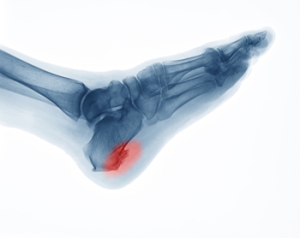

Possible Relief Methods for Heel Spurs

People who experience heel pain may be aware that they might have a heel spur. A heel spur can happen as a result of wearing shoes that do not fit correctly, or from starting a new training regimen. Additionally, heel spurs may develop from standing on hard surfaces for extended periods of time throughout the day. A heel spur is defined as a bony growth that extends from the underside of the heel bone. Relief may be found when appropriate shoes are worn, and the activity that caused the heel spur is ceased. In severe cases, surgery may need to be performed for permanent removal. If you are afflicted with a heel spur, it is strongly suggested that you speak with a podiatrist, who can determine what the best course of treatment is for you.

Heel spurs are formed by calcium deposits on the back of the foot where the heel is. This can also be caused by small fragments of bone breaking off one section of the foot, attaching onto the back of the foot. Heel spurs can also be bone growth on the back of the foot and may grow in the direction of the arch of the foot.

Heel spurs are calcium deposits that cause bone protrusions on the heel bone. Heel spurs are usually associated with plantar fasciitis, which occurs when the plantar fasciitis in the foot becomes inflamed. Typically, heel spurs don’t cause any symptoms. However, they can produce chronic or intermittent heel pain. Those who have had the condition often describe the irritation as a stabbing pain.